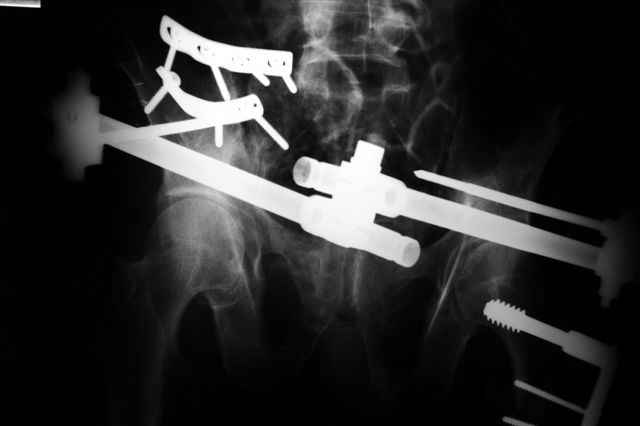

Вчера прооперировал больного.

Попытка низвести половину таза на тракционном столе ( скелетное вытяжение за бедро) безуспешная.

из переднего доступа добрался до правого КП сочленения , все запаяно костью, с помощью 2 шанцев винтов в крестец и подвздошную кость и элеватора репозиция, контроль ЭОП

и двумя пластинами фиксация.

Спереди, аппарат как рекомендовал Джолдас.

Снимки плохого качества( очень темные) завтра переделают и пришлю на конференцию.

На мой взгляд, смещение устранено и фиксация выглядит вполне анатомичной.

В приложении послеоперационные картинки.